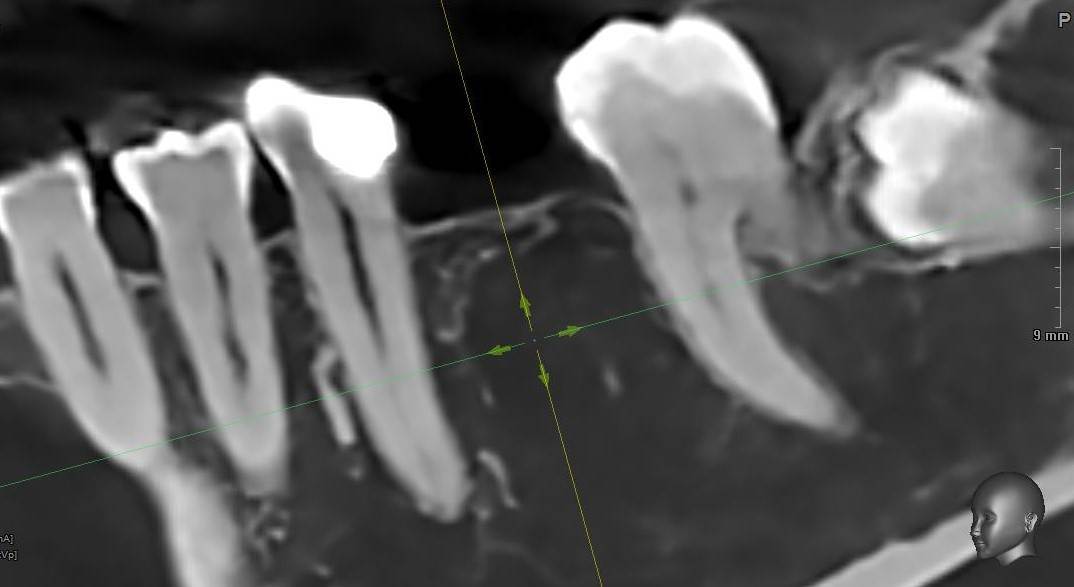

Aquarius Опубликовано 19 часов назад Поделиться Опубликовано 19 часов назад Здравствуйте, коллеги! Рад всех видеть - читать! Надеюсь никого не призвали-забрали)) Возник вопрос . В практике нередко бывают ситуации, которые немного выходят за рамки , скажем так , обычных кейсов. К примеру - как вы поступаете в случае имплантации в зонах очень мягкой кости, в нетипичных для этого анатомических областях ? К примеру не бугор в/ч, а тело нижней челюсти у соматически здоровой, не курящей пациентки средних лет? Имплант JD . Недопреп почти в 2 раза по диаметру - имплант проваливается в тело и в сторону. Собственно вопрос - подключаете фарму? Якобы спорный Остеогенон? Вит Д3? Или как то по другому выходите из ситуации? Спасибо Ссылка на комментарий